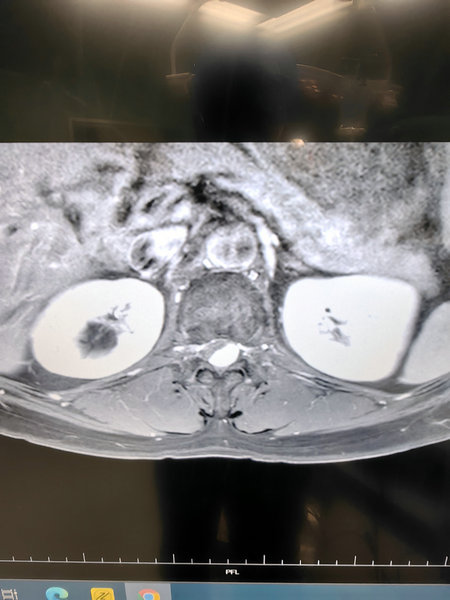

50岁的魏女士,半年前开始出现左下肢疼痛,本以为单纯的腰间盘突出,但右下肢也逐渐出现了疼痛,为查找病因、及时诊治,魏女士遂到齐医附属二院求治,经核磁共振检查,结果显示魏女士的胸12-腰1之间椎管内生长了肿瘤,于是魏女士的家属带着片子找到了齐医附属二院骨外三病区,刘艳楠副主任结合片子以及对患者进行专科检查后建议手术治疗,经过完善术前检查,手术顺利进行,术后恢复良好,魏女士双下肢疼痛症状消失,走路时两条腿也变得轻松了。

椎管内肿瘤的临床表现在疾病的初期阶段可能并不典型,与退行性疾病表现类似,仅表现为疼痛,或可以没有任何症状,但当出现肢体麻木或无力时,应当怀疑椎管内肿瘤的可能,及时行MR检查以明确诊断,除部分髓内肿瘤和硬膜外肿瘤为恶性外,大部分椎管内肿瘤均为良性肿瘤,虽然是一种良性肿瘤,但随着肿瘤的不断生长会逐渐造成脊髓和神经的压迫,导致受压平面以下的肢体运动、感觉、反射、括约肌功能以及皮肤营养出现障碍。早期手术效果明确,手术效果好,患者神经功能一般均可以得到明显的改善。